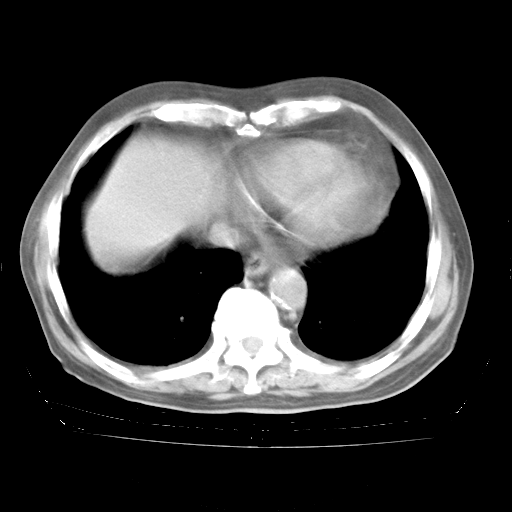

今天部分检查

轻微咳嗽,无痰,(体温正常时)R20次/分,P75次/分,双肺底、腋下可闻及少量捻发音。下肢轻度浮肿。

腹部B超:胆囊壁增厚,肝、胆、胰、脾、肾无异常,肠系膜淋巴结、腹膜后淋巴结无增大。

ECG:右心室增大

心脏超声检查:无右心室增大。